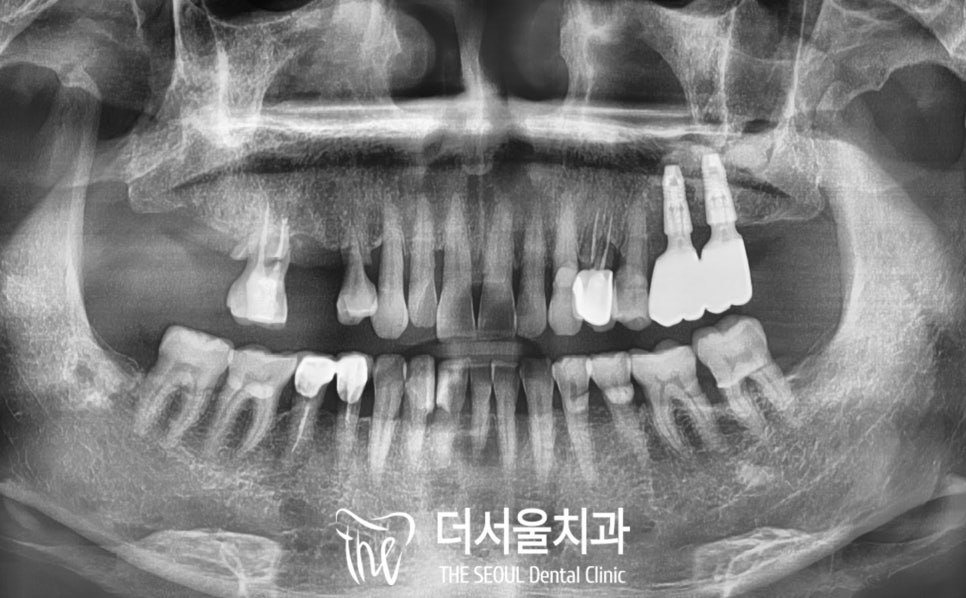

구강을 살펴보면

오른쪽 위 어금니가 없거나

잇몸이 좋지 않아

염증이 있는 것으로 보입니다.

파노라마를 찍어서 살펴보면

이가 빠진지 꽤 오래되셨는지

주변으로 잇몸뼈가 퇴축되고 있었습니다.